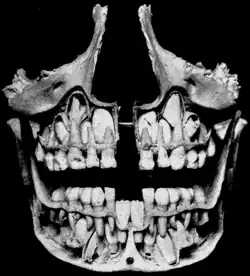

Dočasné zuby se začínají formovat během embryonální fáze těhotenství. Vývoj dočasných zubů začíná v šestém týdnu vývoje zubní ploténkou. Tento proces začíná ve střední čáře a rozšiřuje se do zadní oblasti. Když embryo dosáhne věku osmi týdnů, nachází se již na horním a dolním oblouku po deseti pupenech, ze kterých se později stanou dočasné zuby. Tyto zuby pokračují v růstu, dokud se neprořežou v ústech. V dočasném chrupu se nachází celkem dvacet zubů: pět na kvadrant a deset na jeden zubní oblouk. Prořezávání neboli erupce těchto zubů začíná ve věku šesti měsíců a pokračuje během období dočasného chrupu až do věku 25-36 měsíců. Jako první se obvykle v ústech objeví dolní střední řezáky a jako poslední horní druhé stoličky.

Dočasný chrup se skládá ze středního řezáku, postranního řezáku, špičáku, první stoličky a druhé stoličky, po jednom v každém kvadrantu, takže každý tento zub se nachází v ústech celkem čtyřikrát. Všechny dočasné zuby jsou postupně nahrazeny svými protějšky ze stálého chrupu, s výjimkou první a druhé stoličky, které jsou nahrazeny třenovými zuby. V tzv. univerzálním systému označování zubů, používaném v USA, se dočasné zuby označují velkými písmeny A až T.[1] Výměna dočasných zubů začíná kolem šestého roku věku, kdy se v ústech začínají objevovat stálé zuby a nastává období smíšeného chrupu. Prořezávající se stálé zuby vyvolávají resorpci kořenů, při které stálé zuby tlačí na kořeny dočasných zubů, ty jsou rozpouštěny odontoklasty (a okolní alveolární kost osteoklasty), a nakonec vstřebávány tvořícími se stálými zuby. Proces vypadávání dočasných zubů a jejich nahrazení stálými zuby se nazývá exfoliace a může trvat od šesti do třinácti let věku. Ve dvanácti letech už má dítě obvykle pouze stálé zuby.